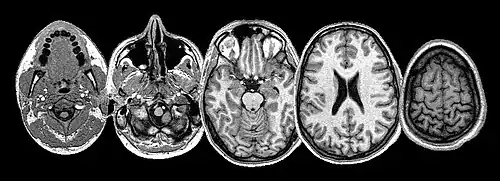

Many brain structures and physiological processes are involved in suffering (particularly the anterior insula and cingulate cortex, both implicated in nociceptive and empathic pain).[29] Various hypotheses try to account for the experience of suffering. One of these, the pain overlap theory[30] takes note, thanks to neuroimaging studies, that the cingulate cortex fires up when the brain feels suffering from experimentally induced social distress, as well as physical pain. The theory proposes therefore that physical pain and social pain (i.e. two radically differing kinds of suffering) share a common phenomenological and neurological basis.